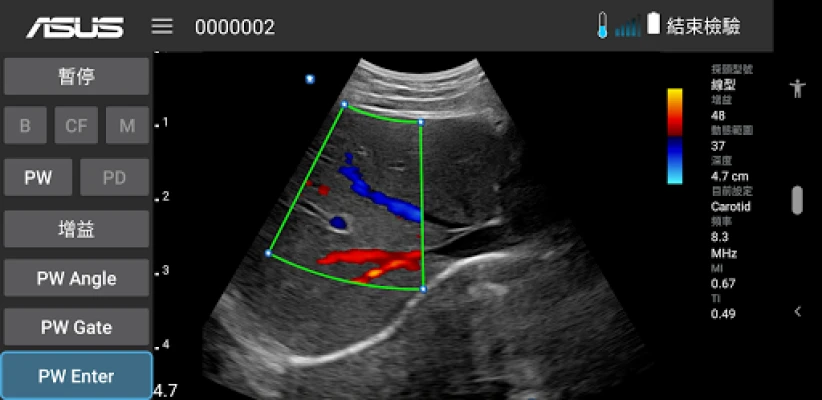

ASUS Portable Ultrasound is a wireless, handheld, pocket-sized imaging tool.

This flexible and feasible APP supports reliable and dependable images for diverse scenarios.